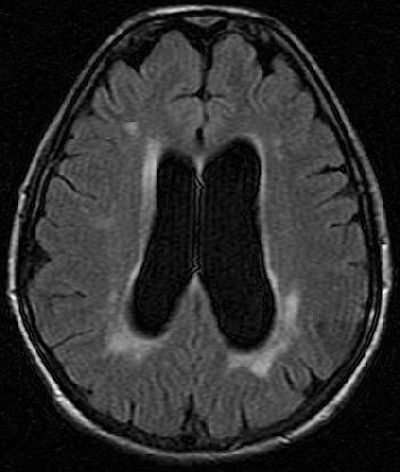

On T2-weighted and T2-weighted FLAIR MR studies, readers should look for hyperintense, asymmetric, deep, and widespread white-matter nodules. If the patient is undergoing treatment, these white abnormalities usually remain unchanged, but may worsen if the person is over age 40, the researchers stated. After therapy, the T1-weighted hypersignal of the deep gray-matter nuclei may disappear, they added.

| A 52-year-old woman with periventricular hyperintense nodules on FLAIR imaging (1.5-tesla system; TR/TE, 9,000/146; inversion time, 2,250 msec; slice thickness, 5 mm). Nodular pattern, although nonspecific, should suggest disease in nonhypertensive patient and is related to cerebral vasculopathy involving long perforating arteries. Lidove O, Klein K, Lelièvre J, Lavallée P, Serfaty J, Dupuis E, Papo T, Laissy J. "Imaging Features of Fabry Disease" (AJR 2006; 186:1184-1191). |